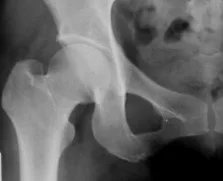

髋关节

是连接人体骨盆和下肢的一个大关节,由股骨头和髋臼组成,他们就像一个倒扣杵和臼,在活动的同时具有良好的承重和稳定性,而其中股骨头由于本身解剖结构的特殊性,最容易受到影响:

股骨头

本身的血供如上图所示,是由较粗的动脉的分支及其末梢来供血的,他们在股骨颈基底部形成一个供血动脉环,而在头部主要依靠这个环发出的细小分支来营养,类似于心脏的冠状动脉,一旦其中形成堵塞,就会直接导致供血支配区的缺血坏死。大量饮酒后,酒精代谢主要在肝脏进行,使脂肪在肝内出现堆积,形成脂肪肝,不断放出脂肪栓子进入血液,脂肪栓子滞留于终末的小血管及软骨下血管床内,引起软骨缺血而坏死;同时酒精代谢过程中产生乙醛等脂质过氧化物,从而引起血管内皮的进一步损伤,形成微小的栓子堵塞血管;加之酒精及其代谢产物的直接细胞毒性作用,饮酒还可造成维生素D代谢紊乱,骨细胞代谢降低,成骨能力减低,发生骨质疏松,导致局部受力面积减少而产生高应力的成骨反应,骨细胞破坏,软骨下出现微小骨折,引起局部骨内压升高和出血,导致骨坏死。这一系列的变化导致股骨头得不到充足的营养供应,在负重下出现的慢性损伤不能及时修复,日积月累逐渐出现股骨头坏死塌陷变形。